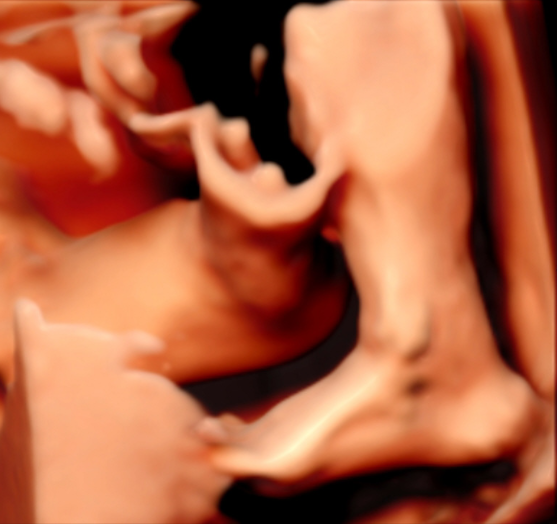

很多准妈妈可能对四维(4D)彩超已经非常熟悉,它能够实时动态地展示宝宝在宫内的活动,让我们看到宝宝打哈欠、伸懒腰的可爱模样,为无数家庭留下了珍贵的第一份“动态影集”。

5D智能彩超拥有更高的分辨率和更强的图像处理能力,能够呈现出接近“IMAX电影画质”的细腻影像 。它采用一种被称为“水晶成像”的技术,能够穿透组织,将胎儿的骨骼、器官和组织结构以极其清晰、立体的形态展示出来。这种高清晰度对于观察胎儿微小的解剖结构细节至关重要,例如手指、脚趾、耳廓形态等,有助于医生发现一些在传统超声下不易察觉的细微异常,为排畸诊断提供了更丰富的视觉信息。

4. 温情互动,一次充满感动的“亲子会面”

除了严谨的医学诊断价值,5D彩超也为准爸妈们带来了无与伦比的情感体验。通过高清逼真的动态影像,您可以清晰地看到宝宝的每一个细微表情和动作,仿佛他(她)就在眼前。这份提前到来的“亲密接触”,不仅能极大地缓解孕期的焦虑,更能加深家庭成员与未出世宝宝之间的情感连接,让等待的每一天都充满更具体的幸福感。